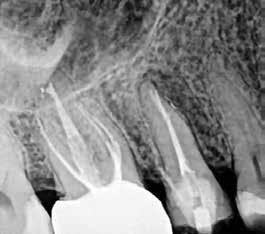

1. ábra: A 15-ös foggyökér meziális felszíne mellett látható radiolucens elváltozás, illetve a felvételen látható a korábban behelyezett gyökértömés, a parapulpális csap segítségével elhorgonyzott csonkfelépítés és a fogat borító cirkonkorona. –2. ábra: A saggitalis irányú CBCT-metszeten jól megfigyelhető az állcsontgerincet elérő radiolucens elváltozás. – 3. ábra: Az axiális irányú CBCT-metszeten egyértelműen látható a kezeletlen palatinális gyökércsatorna, valamint a radiolucens elváltozás mezio-disztális kiterjedése is jól megítélhető. – 4. ábra: A palatinális gyökércsatorna szelektív endodonciai kezelése során először gyógyszeres zárás került behelyezésre. – 5. ábra: A gyógyszeres zárás során alkalmazott kalcium-hidroxid alapú paszta a szulkuszon keresztül a szájüregbe extrudálódott. – 6. ábra: A gyökértömő anyag a középső és apikális gyökéri harmad határán lévő laterális csatornán keresztül a periapikális térbe extrudálódott. 7. ábra: A kezelések befejezését követően 4 évvel készült röntgenfelvételen jól látható a csontállomány gyógyulása és a fiziológiás gyökérhártyarés újbóli kialakulása. –8. ábra: A peroperatív CBCT-felvétel alapján készített koronális irányú metszeten jól látható a gyökércsúcs körül lévő periapikális felritkulás. – 9. ábra: A kezelések befejezése után 4 évvel készített CBCT-felvételen a gyulladásos lézió teljes megszűnése észlelhető.

A CBCT-készülékek endodonciai alkalmazásának talán az az egyik legnagyobb előnye, hogy így olyan anatómiai struktúrák is láthatóvá válnak, amelyeket egyébként nem tudnánk detektálni panoráma, cephalo, vagy periapicalis felvételek segítségével. Mivel a CBCT-felvételek kiértékelése számítógép segítségével történik, így a felvételek vizsgálata során lehetőségünk van az adott területet több nézőpontból és több síkban is megvizsgálni. 2015 októberében egy korábban a rendelőnkben kezelt 55 éves férfi páciens azzal a céllal kereste fel ismét a rendelőnket, hogy másodvéleményt kérjen egy jobb felső kvadránsban található fogával kapcsolatban. Egy másik rendelőben történő vizsgálat során a panaszos fog törését vélelmezték és a fog eltávolítását javasolták, illetve arról is beszámolt, hogy az elmúlt hét során ezen a területen egy puha duzzanat is kialakult. A klinikai vizsgálat során a jobb felső első és második kisőrlő között (14–15) egy fluktuáló duzzanatot észleltünk az áthajlásban. Az 15-ös fog mesialis oldalán 12 mm mély tasakot szondáztunk. A páciens által hozott periapicalis felvételen a 15-ös fog gyökércsúcsának mesialis részén egy nagy kiterjedésű radiolucens elváltozás volt észlelhető (1. ábra). A saggitális síkban vizsgált CBCT-felvételen (Carestream CS 9000, Carestream Dental) a lézió valódi kiterjedése is láthatóvá vált (2. ábra). A megelőző endodonciai kezelések során csupán a bukkális csatorna került detektálásra és gyökértöméssel való ellátásra. Az axiális irányú CBCT-szeleteken egyértelműen látható volt az ellátatlan palatinális gyökércsatorna (3. ábra)

Először kalcium-hidroxid alapú ideglenes gyógyszeres zárás került a palatinális csatornába (UltraCal XS, Ultradent Products; 4–5. ábra), amelyet 6 hét után a végleges gyökértömés elkészítése előtt eltávolítottunk. A gyökértömés elkészítése során meleg vertikális kondenzációs technikát alkalmaztunk. Radiológiai felvételen megfigyelhető volt, hogy a gyökértömő anyag egy laterális csatornán keresztül kis mennyiségben a periapicalis térbe extrudálódott (6. ábra). A 4 évvel később készített kontrollfelvételeken a lézió gyógyulása volt megfigyelhető (7–9. ábra). A vizsgálati eredmények és a kezelés kimenetele egyértelműen igazolta, hogy nem gyökérfraktúrával álltunk szemben, tehát a kezdeti diagnózis tévesnek bizonyult. Ez is azt erősíti, hogy korlátozott mennyiségben rendelkezésre álló adatok alapján nem lehet pontos diagnózist felállítani. Manapság szinte elengedhetetlen a CBCT-felvételek endodonciai beavatkozások során történő használata, feltéve, ha ezek elkészítése során az ALARA elv (as low as reasonably achievable) betartásra kerül.